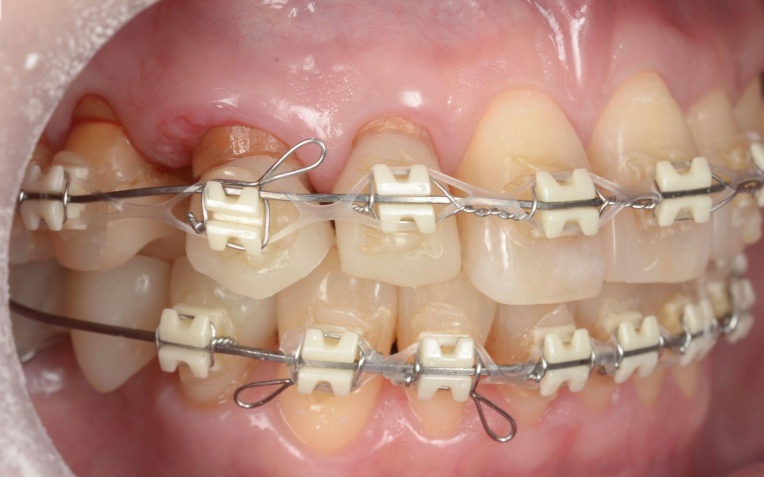

折れている歯を一時的に利用しながら、受け口傾向にある噛み合わせが改善するよう、歯の位置を少しずつ調整していきました。

矯正治療中は定期的に来院いただき、装置の調整を行います。

歯や歯茎の状態、噛み合わせの変化を確認しながら、目標とする歯並びと噛み合わせに近づくよう治療を進めました。

矯正治療終了後は、整えた歯並びが後戻りしないよう、細いワイヤーを固定して歯並びを安定させる装置「リテーナー」を装着しました。

治療中